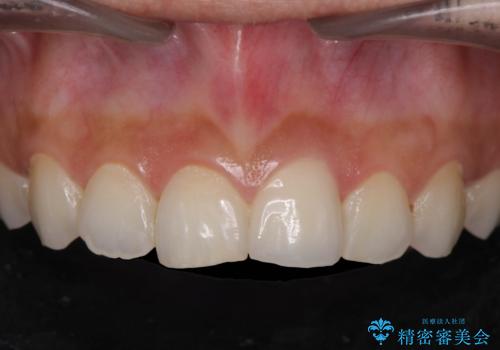

- 16万円(仮歯・ファイバーコア・ジルコニアクラウンスペシャル)費用は治療当時の料金となります

セラミック治療を行う前にきっちりと根管治療を行うことが長期的に持つ可能性を高めます。